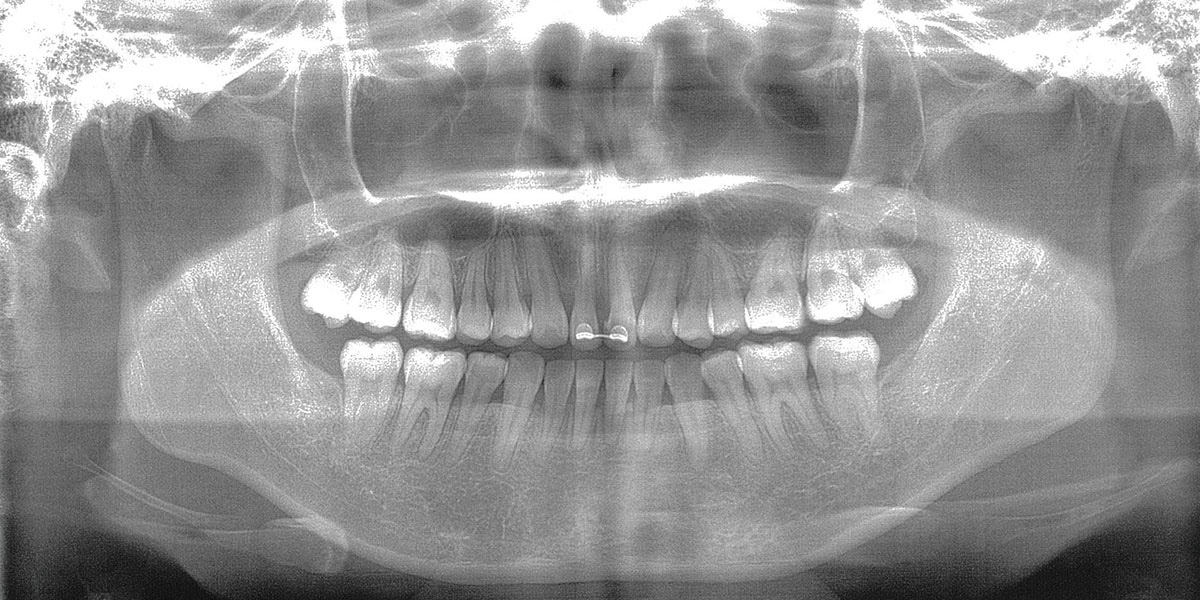

■ レントゲン(治療前)